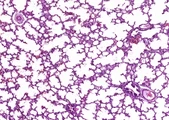

![]() | rozedma pęcherzykowa płuc | 50%